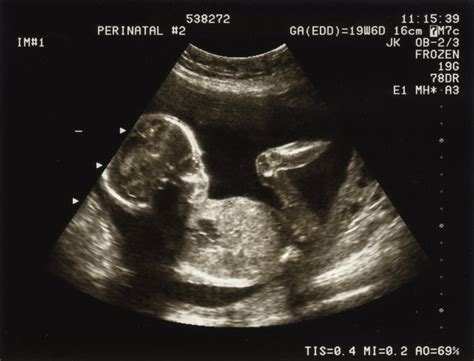

Este important ca femeile să înțeleagă că, deși multe dureri din primul trimestru sunt normale, orice îngrijorare justifică o consultație medicală. Medicul poate evalua simptomele în contextul istoricului medical individual și poate efectua investigații suplimentare, cum ar fi ecografia transvaginală sau dozarea hormonului beta-hCG, pentru a exclude complicațiile grave.